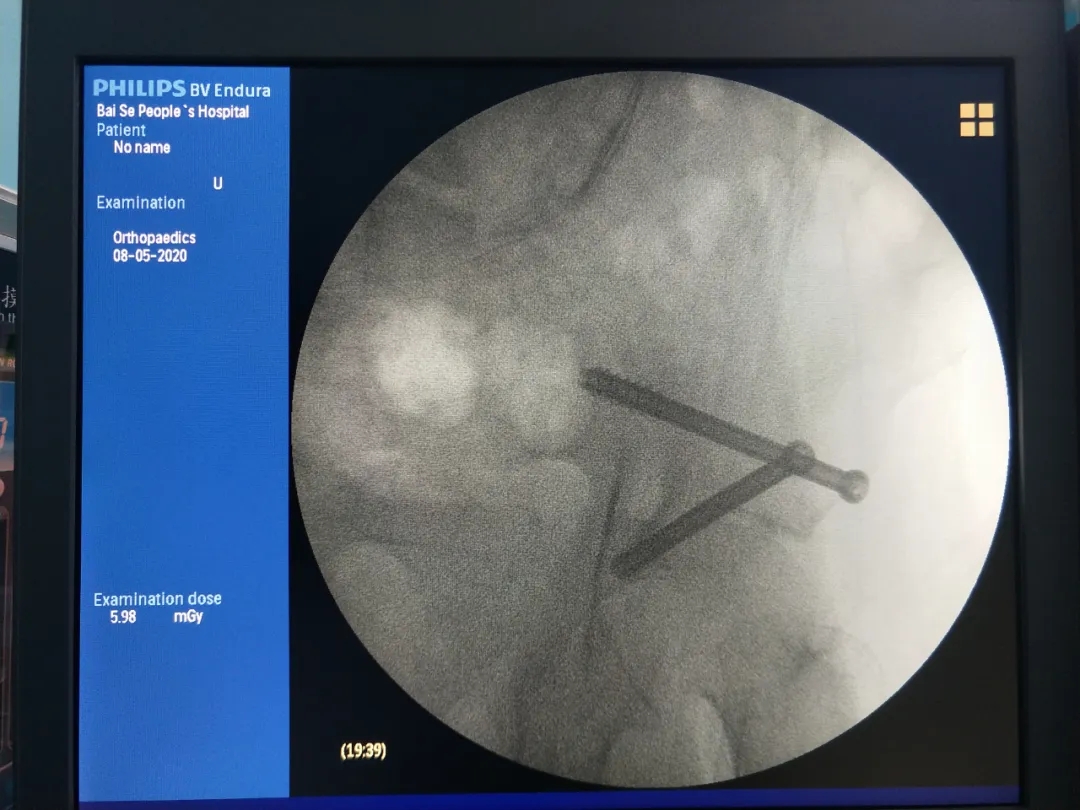

开展天玑?骨科手术机械人辅助下髋臼骨折微创内牢靠术通过天玑?骨科手术机械人机械臂的准确运动,,,,,,仅在手术部位外皮部打入一个“眼”,,,,,,通过天玑?骨科手术机械人的精准定位,,,,,,准确地将空心螺钉置入。。。。。。此术式针对髋臼骨折来说,,,,,,创伤这么细小——手术切口约1cm、出血量仅为2ml,,,,,,确实令人赞叹。。。。。。

术中定位

术中第二枚螺钉准确抵达目的位置